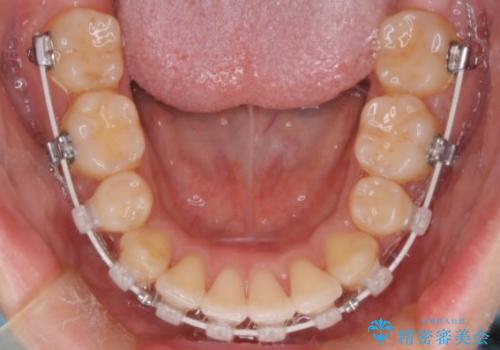

- 前歯の突出が強く、口元が前に出ている印象を改善するため、上下左右の第一小臼歯(4番)を抜歯する矯正治療を計画しました。抜歯により得られたスペースを利用して、前歯を後方へと移動させて整列します。治療には目立ちにくい透明な審美ブラケットとワイヤーを使用し、毎月1回の調整を行いながら徐々に歯を動かし、約2年で口元全体を整える計画としました。

前歯が前に出ているため口元が突出し、唇が閉じにくいなどの悩みを抱えておられました。治療にあたり上下左右の第一小臼歯を抜歯し、十分なスペースを作ることで前歯を効果的に後方へ移動させました。装置には透明で目立ちにくい審美ブラケットを採用し、治療中の審美的ストレスを軽減しました。定期的な調整を通じて無理なく確実に歯列を整え、前歯の突出感を解消。治療後は口元の印象が自然で美しく改善され、患者様には非常にご満足いただけました。